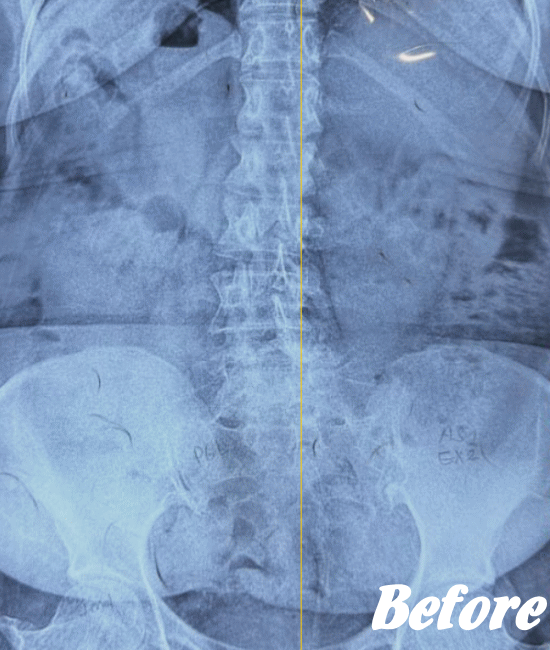

レントゲン、CT、MRIといった画像診断などで坐骨神経痛の原因となる病気(例えば、ヘルニアや脊柱管狭窄症など)が見つかれば、その治療を行います。原因となる病気が見つからない場合は、第一選択肢として、保存療法が適応されます。

HALOカイロプラクティック☆平和島整体院では、仙腸関節や腰、股関節などの部位を解剖学的に正しい状態へ戻すことで、筋肉をゆるめ、関節の詰まりを広げ、圧迫されてしまった神経を解放し、痛みや痺れのない状態へと回復させます。

また、首(頚椎)の歪みにより腰に負担がかかることで坐骨神経痛を発症することもあるため、首も調整します。

ただし、歩行に支障をきたすような激しい痛みの場合は、「股関節のズレが酷い」「腰椎の椎間が詰まっている」「ヘルニアが突出している」「仙腸関節が炎症を起こしている」…等々、通常よりも症状が悪化しているため施術回数が長引くことをご理解いただいたうえで、当院へお越し下さい。